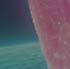

b) Análisis radiográficos, periapicales, ortopantomográficos, oclusales, lateral de cráneo, anteroposterior de cráneo.

c) Estudio y análisis tomográfico en tercera dimensión del cráneo a nivel maxilar y mandibular (Figura 24).

24.

Figura

1. La existencia y presencia de todos los elementos anatómicos craneodentofaciales (Figura 26).

3. Los desplazamientos óseos, como consecuencia de su crecimiento endocondral o intramembranoso en las diferentes zonas o áreas de remodelación, aposición y reabsorción (Figura 27).

Todos los cambios dimensionales de los huesos faciales y su consecuente movimiento y remodelación, están íntimamente relacionados con los estímulos fisiológicos que activan las matrices funcionales de crecimiento, por la presencia de todos los elementos anatómicos (como los caninos), de manera adecuada, en coordinación con los demás elementos que conforman el sistema estomatognático y el sistema respiratorio35,36 (Figura 28).

Al estar ausente algún germen dental (como los laterales superiores permanentes y/o premolares de ambas arcadas, “los de mayor incidencia”),10 se inhibe la estimulación adecuada en el desarrollo óseo de esa zona específica, ya que al no existir el germen dental, la matriz ósea inhibe su crecimiento en esas zonas en específico11 (Figura 29).

maxilomandibulares, 17 las cuales propician alteraciones en el proceso del intercambio dentario; en la que una reducción de los espacios necesarios para el acomodo de los caninos y de otros órganos dentales en las arcadas, retrasa e impide que el impulso natural propio de la formación radicular como empuje fisiológico, impidiendo el desplazamiento y la erupción del canino en tiempo y una posición ideal dentro del arco dental (Figura 30).

Sumado a lo anterior, la retención generada dentro del macizo óseo basal altera su posición en angulación y dirección correcta de erupción. Situación que en ocasiones daña las raíces de los dientes adyacentes al canino y que finalmente podrá quedar incluido, en el peor de los casos, cuando no encuentra una salida de emergencia hacia el paladar o el vestíbulo12 (Figura 31).

consideraciones a tomar muy en cuenta como factor etiológico en la inclusión del canino (Figura 32).

Por otro lado, al haber una pérdida prematura de un diente deciduo, además de generar una disminución de la longitud del arco dental, la biomecánica fisiológica propia de nuestro organismo, tiende a cerrar los espacios o brechas generadas por la pérdida de algún órgano dental, mesializando los dientes distales al diente faltante y generando extrusión del antagonista inmediato (Figura 33).

Figura 29.

Figura 30.

Figura 31.

Figura 32.

Alteraciones faciales

Todos los dientes intervienen en la conformación de una oclusión ideal, así como del volumen facial en el tercio medio e inferior de la cara. Es el caso, que la presencia del canino superior permanente en la arcada en el tiempo cronológico adecuado, es muy importante para el desarrollo óseo del tercio medio facial, ya que estimula el crecimiento del maxilar tanto en el área lateral del ala de la nariz bilateralmente, como en la pared anterior del macizo óseo, lo cual, evita el hundimiento facial de la parte inferior del pómulo y la rectificación facial de los músculos en esta área15 (Figura 34).

tercio inferior, al coordinarse con los caninos superiores en todos los movimientos fisiológicos, como la masticación18 (Figura 35).

El desarrollo y crecimiento mandibular a nivel de la rama, cuerpo y parte anterior en la zona del mentón, depende en parte de la presencia del canino, para efectuar correctamente los movimientos esenciales de lateralidad, protrusión, cierre adecuado de la mordida, además de armonizar el desarrollo correcto de la curva en la arcada dental en el plano transversal o de Wilson, así como de la curva sagital anteroposterior o de Spee19,20 (Figura 36).

La dinámica muscular

Figura 33.

Figura 34.

Figura 35.

Figura 36.

4. Los tiempos biológicos en el cierre de crecimiento óseo39 (Figura 38).

Otra consideración a valorar, son los malos hábitos, entre los que se encuentran con más frecuencia los deletereos y que recaen en la mayoría de las complicaciones para la erupción de los caninos. El tiempo, perseverancia, permanencia e intensidad de estos malos hábitos será proporcional a las alteraciones óseas que se generen, parafunciones musculares y respiratorias, desplazamientos dentales y la consecuente maloclusión presente al momento de realizar el diagnóstico definitivo previo al plan de tratamiento22 (Figura 39).

El colapso bilateral en el maxilar es una de las consecuencias más frecuentes de estos malos hábitos y por consiguiente, propicia una reducción en las dimensiones perimetrales del paladar y del arco dental, aumentando la profundización de la bóveda palatina, generando complicaciones a nivel respiratorio entre otras complicaciones, dando resultados no favorables como la respiración bucal,

acomodo no fisiológico lingual, etc.; lo cual, refleja un acompañamiento del subdesarrollo en el cuerpo y rama mandibular, el cual es un factor crítico para el acomodo de los caninos en la etapa del intercambio dental23 (Figura 40).

Figura 37.

Figura 38.

Figura 39.

Figura 40.

1. Arco extraoral, el cual pude ser utilizado con tracción alta, media o cervical.40,41 Péndulo o aparato de Hillgers modificado (Figura 41).

2. Mascara facial (Figura 42).

3. Bionator simple o combinado con lip bumper, entre otros (Figura 43).

Figura 41.

Figura 42.

posicionada en dirección vestibular, ya que solamente el 17% de caninos impactados vestibularmente tienen un espacio suficiente, a comparación de los impactados donde la corona tomó la dirección hacia el paladar, ya que por lo regular en estos casos, el canino deciduo siguió estando presente sin reabsorción alguna, el cual desempeña un papel importante como mantenedor de espacio biológico; sin embargo, genera la necesidad de que el canino busque una salida emergente, que en estos casos es hacia la bóveda palatina44 (Figura 44).

Está indicada cuando el canino está en una posición infraósea, muy apical al plano oclusal y por arriba de la línea mucogingival. Se remueve el tejido óseo palatino que cubre la corona, colocando un apósito quirúrgico, evitando la formación de tejido mucoso, logrando que el diente erupcione por sí mismo46 (Figura 45).

Esta técnica es la más sugerida cuando el canino se encuentre submucoso y alejado del plano oclusal y los resultados a nivel periodontal y estético tengan un mejor pronóstico.47,48

A partir de la realización de un colgajo, se retira en caso de ser necesario, el hueso que cubre la corona del canino, colocando un aditamento que permita traccionar al diente incluido, cuando el periodo de cicatrización haya concluido. Paso seguido se colocarán los aditamentos de

anclaje para movilizar de forma controlada en fuerza y dirección correcta al canino incluido hacia el arco dental.

Figura 45.